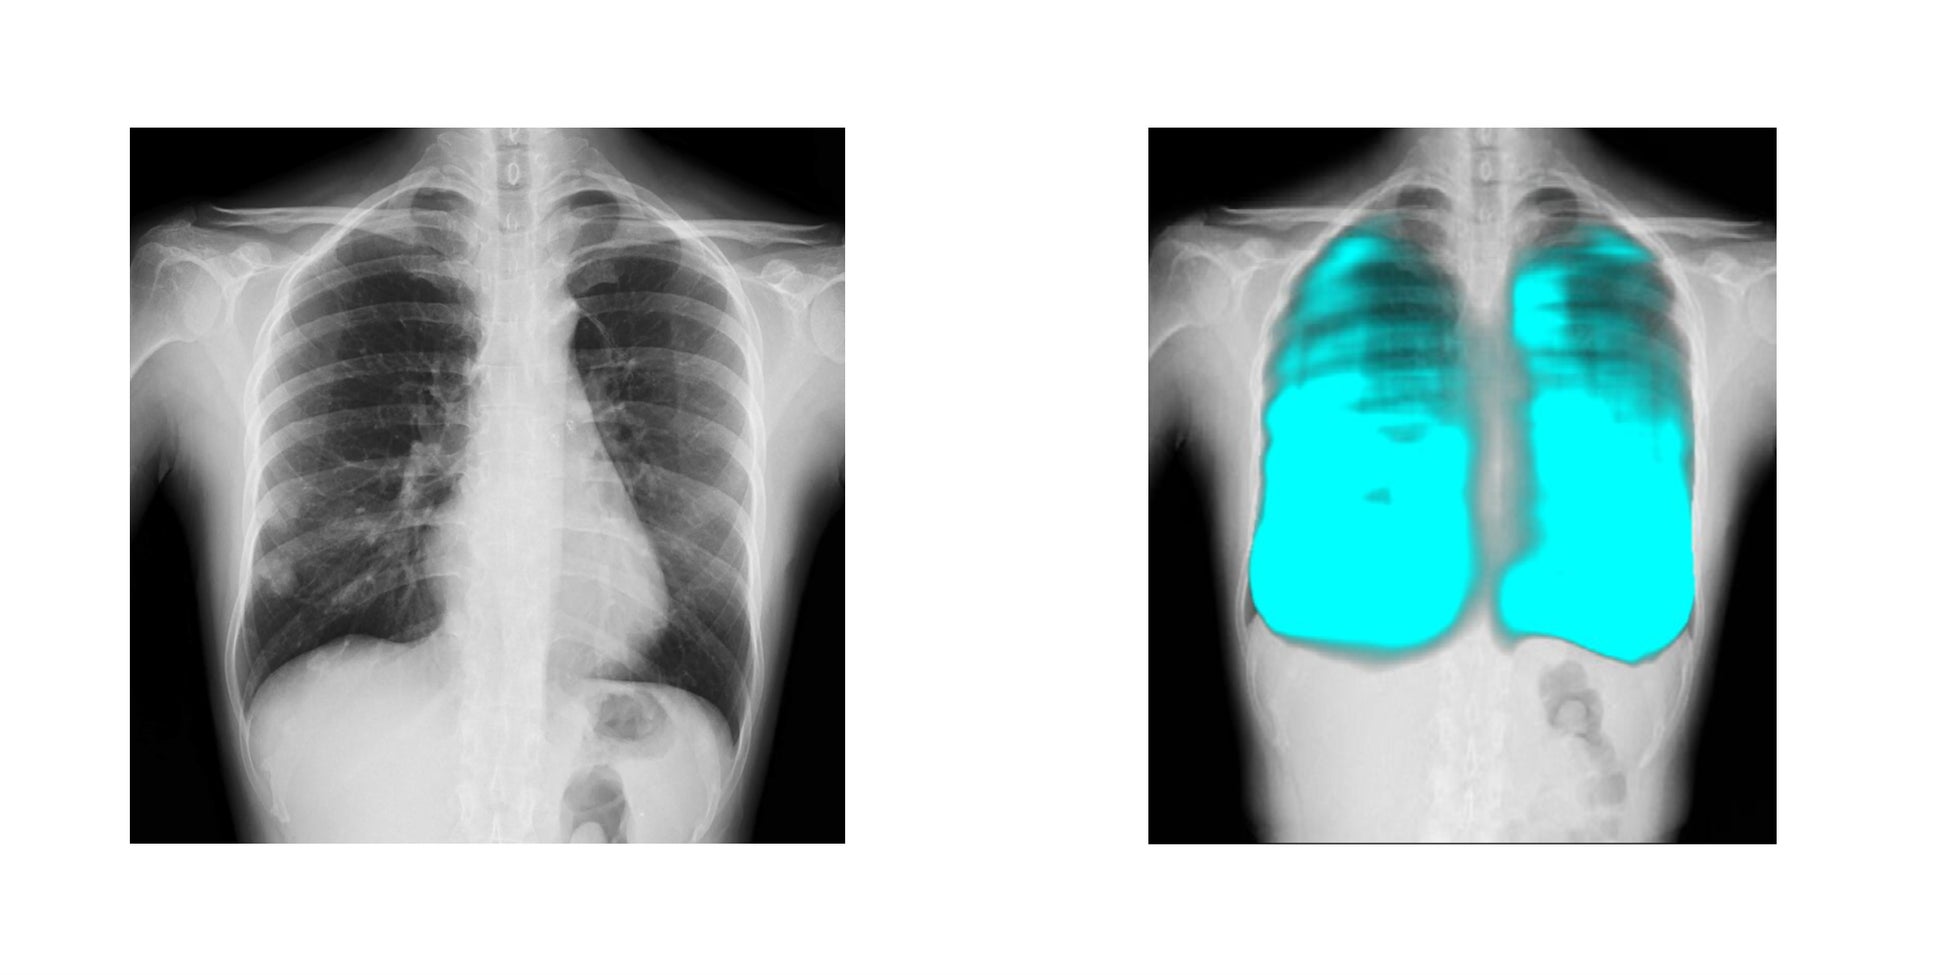

コニカミノルタのX線動態解析技術/イメージングAI技術と、FPTの高度なAI技術を活用し、呼吸器疾患の診断支援、医療レポートの自動生成など新しい診断技術の確立を目指します。コニカミノルタ独自のX線動態解析は、世界で300件以上の特許を取得しており、既に400台以上の販売実績があります。ベトナムの医療イノベーションとデジタル変革による呼吸器疾患対策を推進することで、国民の健康と医療従事者の負担軽減に貢献します。

簡易かつ高度なX線動態解析画像を用いた呼吸器疾患に関する医療指標の開発と、AI診断支援ツールの開発による呼吸器疾患の早期診断機会創出

「X線動態解析」について

コニカミノルタはデジタルX線動態撮影および動態解析を、新しい”動きの診断”を提供するソリューションとして展開しています。この当社独自の技術「X線動態解析」を搭載したシステムとして、一般X線撮影装置を用いて動画を撮影できるデジタルX線動態撮影システムを開発・提供しており、既に国内外の医療機関で導入実績があります。